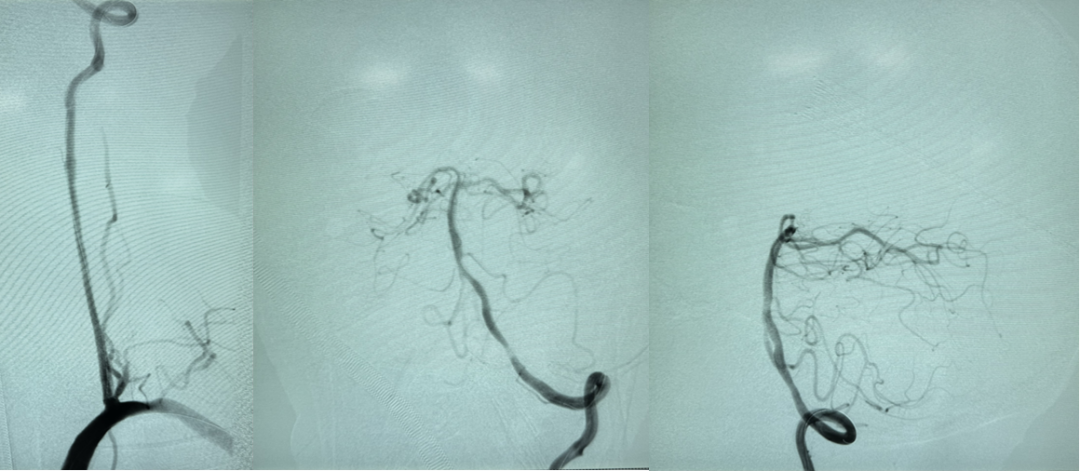

M,60,左侧小脑梗死,左椎动脉V1-V2段长段闭塞

椎动脉外翻剥脱、椎动脉-锁骨下动脉端侧吻合

椎动脉-锁骨下动脉端侧吻合

介入开通

案例二

左椎V1-V2闭塞 开口自体静脉补片成形

3

案例三

左椎V1-V2闭塞 椎-甲状颈干补片搭桥

14个月复查

案例四

椎动脉支架内再狭窄